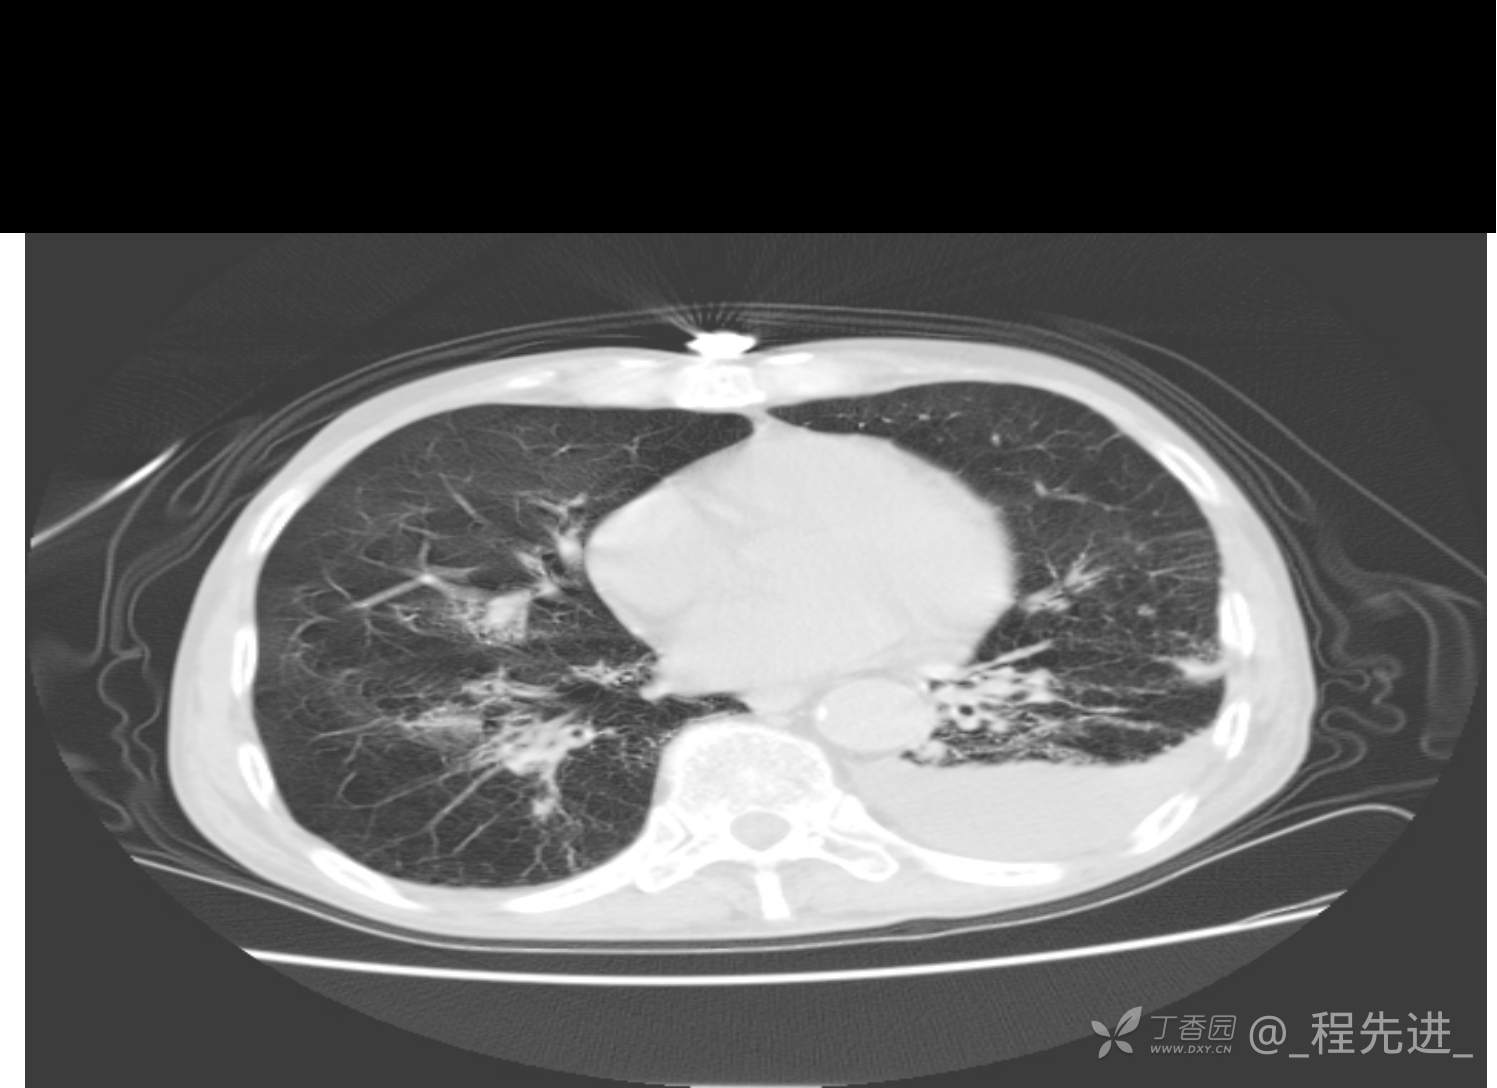

患者性别:男

患者年龄:81岁

简要病史:反复咳嗽、咳痰20余年,加重1周。两肺呼吸音低,可闻及散在干湿啰音。